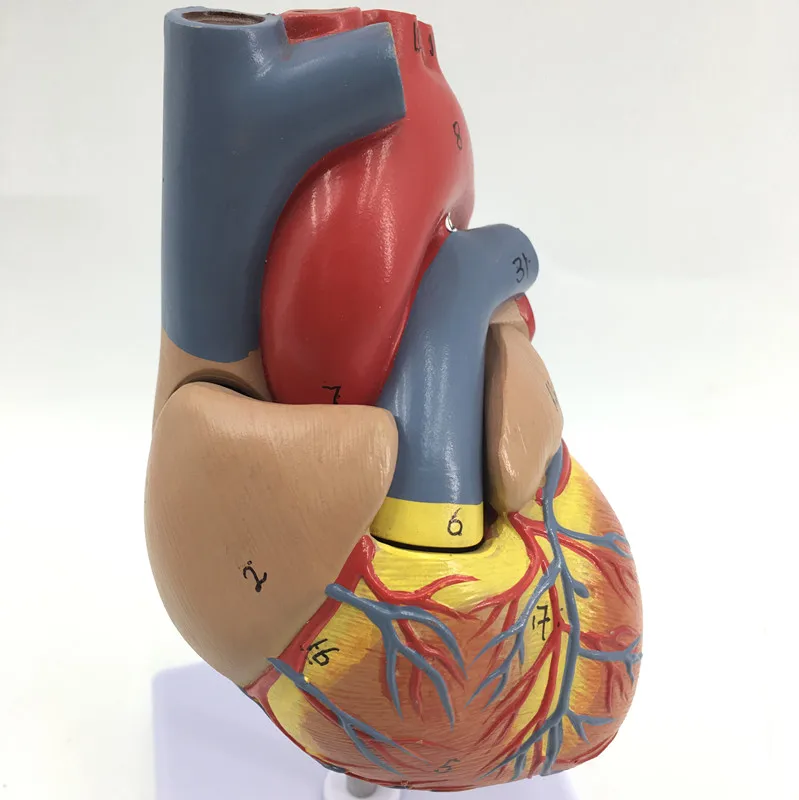

Фотографии и 3D-модели анатомии сердца человека